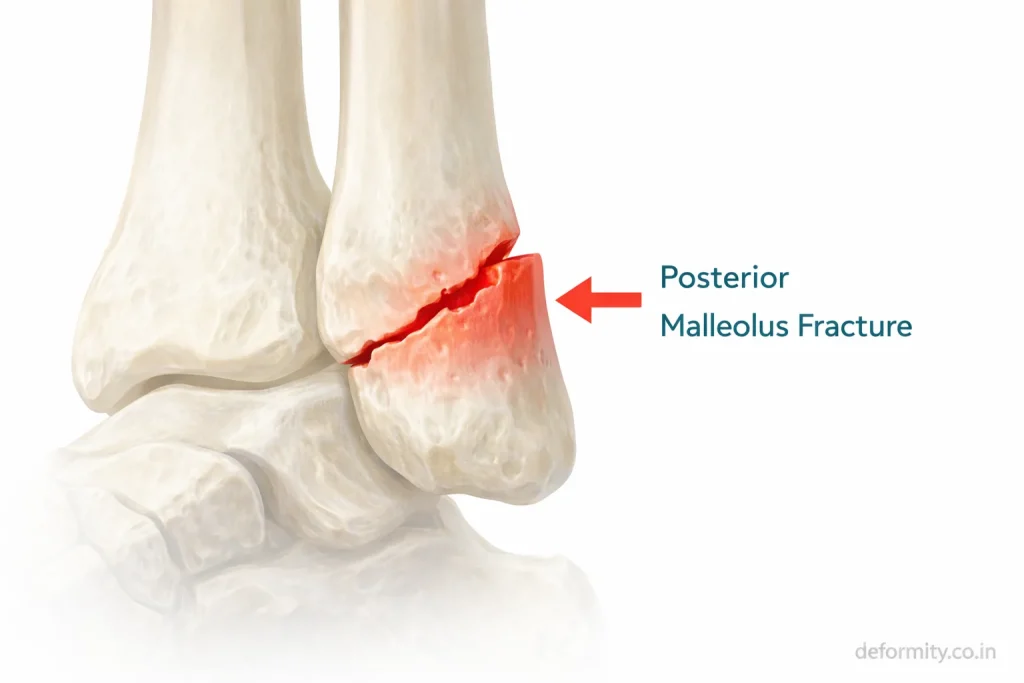

Why the Posterior Malleolus Matters

The posterior malleolus is the back portion of the distal tibia. It forms part of the weight-bearing surface of the ankle joint and provides attachment to the posterior inferior tibiofibular ligament.

When the posterior fragment involves more than 25–30% of the joint surface, surgical fixation is strongly recommended to restore alignment and reduce the risk of arthritis.

Posterior Malleolus Fixation Techniques

Common approaches include:

- Posterolateral approach

- Anterior-to-posterior screw fixation

- Posterior plating

Proper fixation restores joint stability and prevents talar shift.